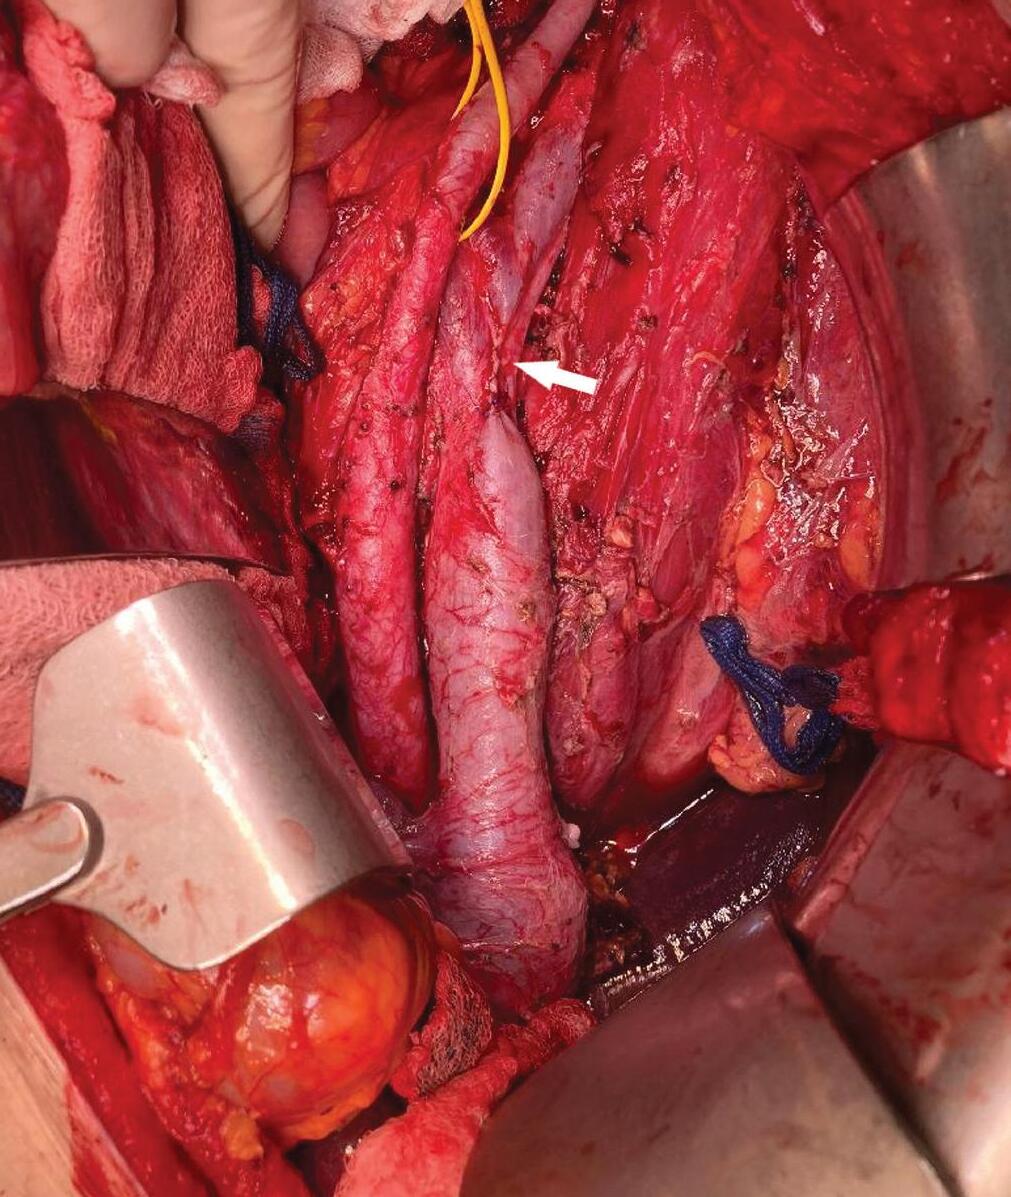

Vazografická obliterace krvácející arterie zádových svalů po bilaterální nefrektomii

Vasographic obliteration of a bleeding back muscle artery after bilateral nephrectomy of polycystic kidneys

Václav Krejčí, Miloš Broďák, Antonín Krajina, Jaroslav Pacovský

Celkem u 5 pac ie ntů v této skupině pak byl k dispozici kromě výsledku cytologie selektivní výplachové moči i výsledek cytologie moči spontánně vymočené. Jednalo se o 4 pacienty s HGUC a 1 pacienta s LGUC. Ve 2 případech (1 případ LGUC a 1 případ HGUC) dala jak výplachová, tak spontánní cytologie moči stejný negativní výsledek (NHGUC). Ve zbylých 3 případech se pak při různých typech odběru moči výsledky cytolog ie rozcházely. Ve 2 případech měla výplachová cytolog ie negativní výsledek, naopak cytologie spontánně vymočené moči byla klasifikována v kategorii SHGUC a HGUC. V 1 případě naopak výplachová cytologie dala atypický výsledek (AUC), cytologie spontánní moči byla negativní (NHGUC).

Skupina 3 – pacienti s močovou cytologií bez bližší specifikace typu odběru urologem

Do poslední skupiny bylo zařazeno celkem 18 pacientů. Jednalo se o případy, kdy na podkladě údajů uvedených na průvodce k cytologickému mater iálu nebylo možné zjistit, jaký způsob kolekce moči byl upřednostněn. V 8 případech se dle WHO 2022 jednalo o pacienty s biopticky verifikovaným LGUC, u 10 pacientů byl potvrzen HGUC. Dle WHO 1973 byli pacienti stratifikováni jako grade 1 ve 3 případech, grade 2 v 7 případech a grade 3 v 8 případech.

Dle Pařížské klasifikace bylo 8 případů kategorizováno jako NHGUC, 2 pacienti splnili kritér ia pro diagnózu AUC, 6 pacientů odpovídalo SHGUC a 2 pacienti byli z močové cytologie stratifikováni jako HGUC. Močová cytologie tak detekovala nádor u 10 z 18 pacientů, tj. souhrnná senzitivita cytolog ie moči pro záchyt UUTUC v této kategorii dosáhla 55 %. Močová cytologie odhalila 7 HGUC (70 %) a 3 LGUC (38 %).

Diskuze

Močová cytologie má relativně vysokou senzitivitu pro detekci HGUC, naopak senzitivita detekce LGUC je nízká a vykazuje značnou interobservační variabilitu [10]. V roce 2016 publikovaná Pařížská klasifikace pro reportování močové cytologie si kladla za cíl jasnou standardizaci jednotlivých cytologických d ia gnostických kritér ií a sjednocení reportování pro přesnější stratifikaci pacientů a jejich následný lepší klinický management [6]. Klasifikace byla velmi dobře přijata odbornou veřejností, což vedlo k její rychlé inkorporaci do rutinní cytologické praxe a diagnostiky [11]. V roce 2021 vyšlo druhé editované vydání klasifikace, které však v porovnání s původní verzí přineslo jen minimální změny [12]. Pařížská klasifikace pro reportování močové cytologie se postavila čelem k nejčastějším a nejvýraznějším úskalím dřívějších klasifikací močové cytologie – zejména se „přiznala“ k limitacím močové cytologie při záchytu LG uroteliálních lézí (uroteliální papilom, papilární uroteliální neoplazie nízkého maligního potenciálu a LGUC) a začala se orientovat preferenčně na záchyt HGUC. Tomu přizpůsobila i název „benigní/negativní“ kategor ie, která od roku 2016 nese název „negativní pro HGUC“. Dále Pařížská klasifikace jasným vytyčením diagnostických kritérií pro jednotlivé diagnostické kategorie napomáhá přesnější stratifikaci nálezů, snižuje interobservační variabilitu při hodnocení a snižuje též počet vzorků hodnocených jako „atypické“ [9,13], tedy v kategorii, která dříve sloužila jako pomyslný odpadkový koš méně jasných případů. I přes jasné nastavení Pařížské klasifikace, soustředící se na záchyt HGUC a spíše „ignorující“ LG léze, dále přetrvávají snahy některých autorů o přesnější cytologickou diagnostiku LG lézí. V literatuře tak lze dohledat popisy určitého spektra různě diskrétních atypií, které mohou být s cytologickým záchytem LG uroteliální léze asociované. Autoři však sami přiznávají, že využití těchto poznatků v rutinní praxi je limitované [14].

Je nutné si uvědomit, že výsledek/nález v močové cytologii je výrazně ovlivněn zvoleným způsobem odběru vzorku moči. V praxi lze odebírat a cytologicky vyšetřovat dva hlavní typy moči – moč vymočenou spontánně a moč získanou instrumentací močových cest (tj. moč výplachovou, moč získanou vymočením bezprostředně po invazivním výkonu na močových cestách či moč získanou z močového katetru). Raab et al. ukázali, že vzorky spontánně vymočené moči by měly vykazovat vyšší specificitu a lehce nižší senzitivitu než instrumentálně získaný vzorek [15]. Výplachový odběr/instrumentace sice resultuje ve vzorek s vyšší celularitou a lepší prezervací buněk, instrumentace však generuje artefakty, které dle některých studií vedou k falešně pozitivnímu výsledku (atypický/suspektní výsledek) vyšetření až v 15,6 % případů [16]. Proto je důležité uvádět způsob, jakým byl vzorek moči odebrán, na průvodní list k cytologickému materiálu. Informace o typu odběru je pro objektivní posouzení vzorku patologem absolutní nutností. Typ odběru moči se výrazně promítá do

cytologických znaků zastižených ve vzorku, které mohou být při neznalosti typu odběru obtížně interpretovatelné.

Močová cytologie je některými pracovišti využívána při záchytu UC zejména dolních močových cest (v rámci primodiagnostiky, ale i k dispenzarizaci pacientů), většinou však pouze jen jako doplňková metoda. V rámci dolních močových cest je senzitivita močové cytologie při detekci HGUC v literatuře uváděna v rozmezí 40–84 % při specificitě 73–100 % [8,17,18].

Zlatým standardem pro d ia gnostiku UC je však invazivní vyšetření (cystoskop ie ) a odběr b io ps ie. Atraktivita možného širšího využití cytologie moči tkví v neinvazivitě vyšetření a menší finanční náročnosti (tyto výhody pochopitelně odpadají v případě provedení výplachové cytologie při cystoskopii).

Zkušenosti s využitím močové cytologie při detekci UUTUC (jak literární, tak i z rutinní praxe) nejsou při nižším výskytu tumorů horních cest močových většinou příliš rozsáhlé. Některá literární data však poukazují na nižší senzitivitu močové cytologie pro detekci HGUC v horních močových cestách oproti UC močového měchýře [8,19]. Na vině může být fakt, že při cytologické detekci UUTUC js ou urotelie (benigní i neoplastické) během putování z pánvičky/ureteru vystavené relativně hostilnímu působení moči po delší dobu. Navíc se na jejich prezervaci negativně podepisuje také mechanické působení ureterální peristaltiky. Senzitivita močové cytolog ie pro záchyt UUTUC je tak v různých studiích uváděna v širokém rozmezí od 43 do 92 % [2,17–22]. Autoři Potretzke et al. provedli statistický souhrn a metaanalýzu prací zabývajících se specificky selektivní výplachovou cytologií při screeningu UUTUC a uvádějí, že průměrná senzitivita záchytu UUTUC z močové cytologie (při korelaci s finální bioptickou diagnózou) u selektivních výplachových vzorků dosahuje 53 % (při celkovém rozmezí 21–77 %) [20].

V literatuře bývá diskutovaná problematika volby nejvhodnější metody odběru moči pro cytologické vyšetření při detekci UUTUC, výsledky jsou relativně konfliktní a lze dohledat práce preferující instrumentální (výplachový) odběr i moč spontánně vymočen ou. Stud ie ně kte rých kolektivů tak ukazují, že cytologické vyšetření provedené z výplachového vzorku má v případě UUTUC lepší výtěžnost než cytologie spontánně vymočené moči [19,23–25]. Konkrétně autoři Zhang et al. ve své práci porovnávali senzitivitu výplachové a spontánní cytologie u retrospektivně vyhledaných HG UUTUC. V případě spontánních vzorků moči byla senzitiva záchytu HGUC 27 %, při započtení i atypických kategorií do celkového výsledku pak senzitivita dosáhla až 83 %. U výplachových vzorků byl HGUC správně detekován v 62,5 % případů, při započítání atypicky hodnocených případů až u 100 % [2]. Zheng et al. ve své studii zabývající se diagnostikou UUTUC ze selektivní výplachové cytologie popsali senzitivu a specificitu detekce HGUC 78, resp. 91 % (při započtení SHGUC a HGUC kategorie) [26]. V práci autorů Simon et al. senzitivita

Ces Urol 2025; 29(1): 22– 28

cytologického vyšetření při detekci HGUC ze selektivních výplachových vzorků dosahovala 19 %, při započtení cytologických kategorií SHGUC a AUC potom až 85 % [23]. Kolektiv autorů v čele s McIntire ve své práci reportuje 82% senzitivitu při detekci HGUC z výplachových vzorků [9]. Chen et al. při hodnocení výplachových vzorků dosáhli při detekci HG UUTUC senzitivity a specificity 71,4, resp. 91,9 % a senzitivity/specificity při detekci LG UUTUC 21,4, resp. 100 % (při započítání pozitivních a atypických diagnóz) [25]. V literatuře jsou však k dohledání i práce, které přínos selektivních výplachových cytologií spíše zpochybňují. Například autoři Dev et al. ve své práci zahrnující 100 pacientů s UUTUC porovnávali výsledky spontánní a selektivní výplachové cytolog ie a došli k závěru, že výplachová cytologie přináší oproti spontánně vymočené moči p ouze zcela marginálně zvýšen ou senzitivitu záchytu [27].

V našem souboru senzitivita močové cytologie při detekci HG UUTUC činila 65, resp. 55 % (spontánní moč vs. instrumentální odběr/selektivní výplach). U pacientů, u nichž způsob odběru moči nebyl urologem specifikován, byla senzitivita cytologie moči pro záchyt HG UUTUC 70 %. Průměrná senzitivita všech tří skupin byla při detekci HG UUTUC stanovena na 64 %. Stejný fenomén pak pozorujeme i v rámci hodnocení senzitivity močové cytologie při detekci LG UUTUC, kdy spontánní moč přinesla senzitivitu 40 %, selektivní výplach 20 % a u pacientů s blíže nespecifikovaným způsobem kolekce moči 38 %. Celková senzitivita močové cytologie pro detekci LG UUTUC odpovídala 36 %. Naše výsledky hovoří ve prospěch spontánních vzorků při detekci LG i HG UUTUC. Relativně nejvyšší senzitivitu močové cytologie u pacientů bez informace o způsobu kolekce moči (skupina 3) lze jen obtížně vysvětlit. Čistě hypoteticky, pokud patolog postrádá základní informace o typu odběru na průvodním listu k cytologickému materiálu, lze počítat s tím, že při diagnostice ke vzorku přistupuje agresivněji (počítá vždy s horší variantou). Je však třeba si uvědomit, že v rámci této studie bylo pracováno pouze s pacienty s finálně verifikovaným UUTUC. Velmi zajímavé by mohlo být statistické zhodnocení falešné pozitivity močové cytologie u pacientů, u nichž následnou biopsií nebyla přítomnost UC prokázána (a zejména pak u pacientů bez specifikace typu odběru moči). Toto hodnocení však není cílem a součástí zde předkládané práce.

Mezi limity naší práce patří retrospektivní charakter studie, malá velikost kohorty (ostatně stejně jako i u většiny podobných dostupných prací, kdy vzácnost výskytu UUTUC nedovoluje vytvořit větší soubor). Další limitací modifikující výsledky studie je i výše komentovaný výrazný selekční bias (využití výsledků močové cytologie jen u pacientů s histologicky prokázaným UUTUC, a nikoliv u všech pacientů s podezřením na UUTUC na základě zobrazovacích metod), kdy při absenci nenádorové kontrolní skupiny lze počítat s nadhodnocením zjištěné senzitivity. Neméně významným faktem ovlivňujícím výsledky studie je i neznalost typu kolekce moči u signifikantní části pacientů (26 %) zařazených do této studie. S podobnými limity se však setkává většina v literatuře dostupných prací. Velké množství proměnných v různých originálních studiích nedovoluje provést jednoduché „head to head“ porovnání výsledků. Jednoznačná odpověď na otázku, který typ kolekce močové cytologie je při detekci UUTUC nejlepší, tak v s ou časné době neexistuje. Jako nejslibnější způsob, jak najít odpověď na tuto otázku, se jeví standardizovaná prospektivní studie s jasně nastavenými inkluzními kritérii, odběrem vzorků, termínovými omezeními a jasně danými diagnostickými algoritmy.

Závěr

Senzitivita močové cytologie pro záchyt UUTUC (bez ohledu na definitivní LG či HG histologickou diagnózu) činila ve skupině se spontánním odběrem moči 50 %, ve skupině pacientů se selektivním výplachem 44 % a ve skupině bez specifikace odběru 55 %. Močová cytologie správně detekovala celkem 64 % HG UUTUC, u LG UUTUC cytologie odhalila tumor v 36 % případů. Senzitivita močové cytologie pro záchyt UUTUC je tak porovnatelná s dostupnými literárními daty pro záchyt UC dolních močových cest a s močovou cytologií obecně, pohybuje se však spíše při dolní hranici v literatuře uváděného rozmezí senzitivity pro močovou cytologii dolních močových cest. Naše výsledky hovoří relativně ve prospěch spontánního odběru moči při detekci UUTUC.

Střet zájmů: Autoři prohlašují, že nemají žádný konflikt zájmů.

Prohlášení o podpoře: Karlova Univerzita Praha, Lékařská fakulta Plzeň (Cooperatio Program, SURG), Institucionální výzkum Fakultní nemocnice Plzeň (FNPl 00669806).

Literatura

1. Williamson SR, McKenney JK, Raspollini MR et al. Invasive urothelial carcinoma. In: WHO Classification of Tumours Editorial Board. Urinary and male genital tumours. Lyon (France): International Agency for Research on Cancer. 5th ed, 2022.

2. Zhang ML, Rosenthal DL, VandenBussche CJ. Upper urinary tract washings outperform voided urine specimens to detect upper tract high-grade urothelial carcinoma. Diagn Cytopathol 2017; 45(8): 700– 704. doi: 10.1002/ dc.23746.

3. Bagley DH, Huffman JL, Lyon ES. Flexible ureteropyeloscopy: diagnosis and treatment in the upper urinary tract. J Urol 1987; 138(2): 280– 285. doi: 10.1016/ s0022-5347(17)43119-3.

4. Pivovarcikova K, Pitra T, Alaghehbandan R et al. Lynch syndrome-associated upper tract urothelial carcinoma frequently occurs in patients older than 60 years: an opportunity to revisit urology clinical guidelines. Virchows Arch 2023; 483(4): 517– 526. doi: 10.1007/ s00428-023-03626-2.

5. Pitra T, Pivovarčíková K, Sedláčková H et al. Lynchův syndrom v rukách urologa. Ces Urol 2017; 21(4): 272– 279. doi: 10.48095/ cccu2017045.

6. Rouprêt M, Babjuk M, Burger M et al. European Association of Urology Guidelines on upper urinary tract urothelial carcinoma: 2020 update. Eur Urol 2021; 79(1): 62– 79. doi: 10.1016/ j.eururo.2020.05.042.